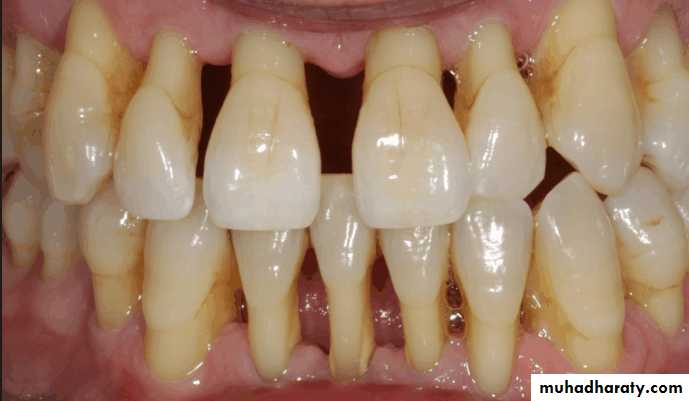

Evaluation of periodontium

Periodontal disease is one of the main etiologic factors in the loss of the teethA removable partial denture placed in the presence of active periodontal disease will contribute significantly to the rapid progression of the disease and the loss of the remaining teeth.

The causative factors must be eliminated, the disease process must be controlled before the fabrication of the prosthesis.

Examination findings that indicate possible need for periodontal treatment include

Pocket depth in excess of 3 mmFurcation involvement

Deviations from normal color and contour in gingiva, indicating gingivitisMarginal exudate

Potential abutment teeth with less than 2 mm of attached gingiva

Pulling of muscle or frena on attached gingiva

Periodontal examination that includes

Determination of pocket depth, examination for evidence of infection or inflammation, the amount of attached gingiva of the prospective abutment teeth is madeThe oral mucosa is examined visually and with palpation for evidence of pathologic change

The examination is made for the presence of tori, exostoses, sharp or prominent bony areas , soft or hard tissue undercuts, enlarged tuberosities.